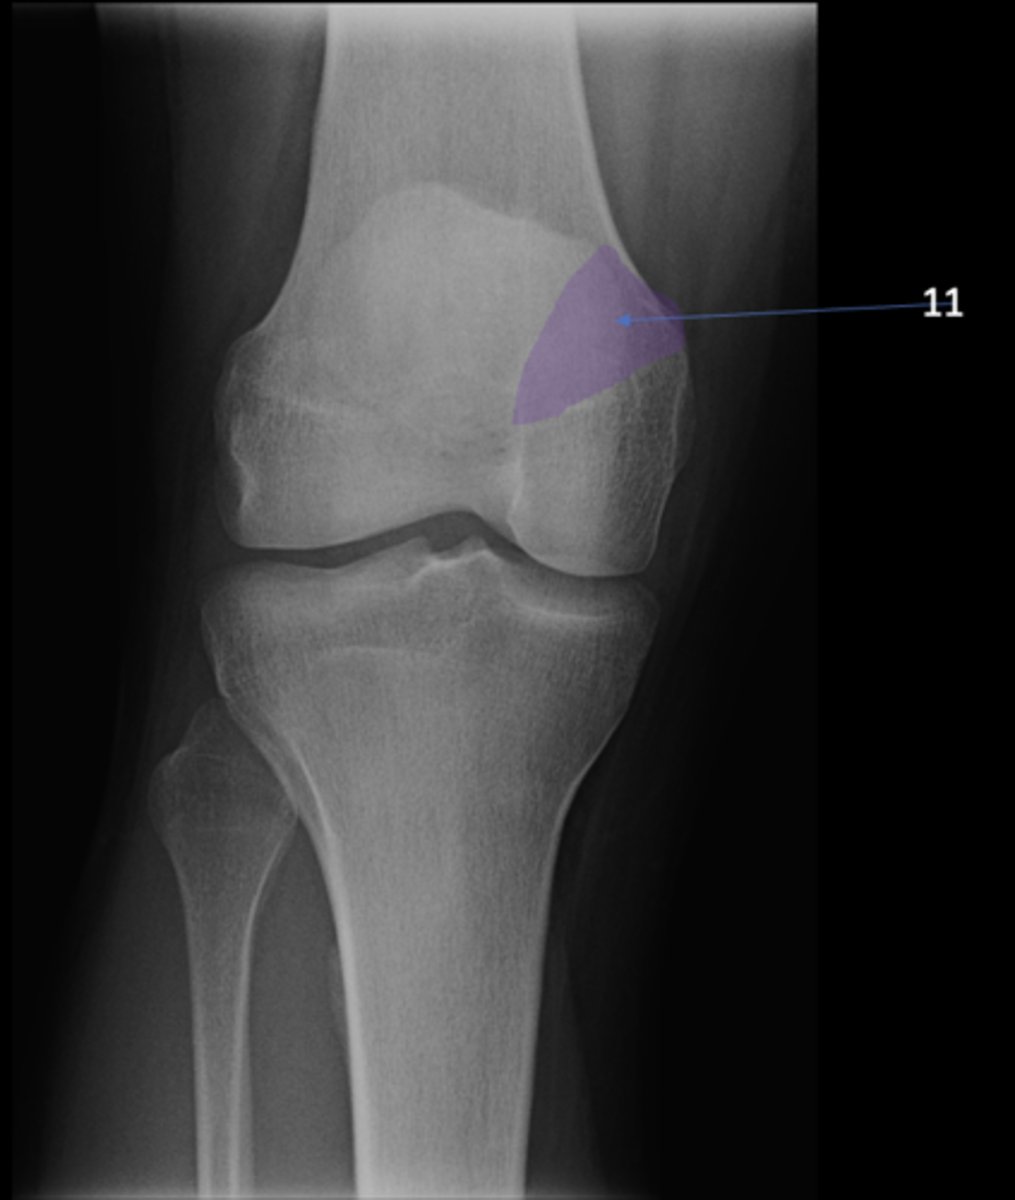

AP knee

View?

<p>View?</p>

6

New cards

Left anterior superior iliac spine

ID 6

<p>ID 6</p>

7

Right ischium

ID 7

<p>ID 7</p>

8

Left ischial spine

ID 8

<p>ID 8</p>

9

Right fovea capitis

ID 9

Fibular head

ID 1

Apex of fibular head

ID 2

Fossa for popliteal tendon

ID 3

Intercondylar eminence

ID 4

Superior aspect of patella

ID 5

Lateral femoral condyle

Medial femoral condyle

Intercondylar fossa

Apex of patella

Lateral femoral epicondyle

ID 10

Medial femoral epicondyle

ID 11

Tibial tuberosity

ID 12

Medial tibial plateau

ID 13

Lateral tibial plateau

ID 14

Medial tibial condyle

ID 15

Lateral tibial condyle

ID 16

Physeal scar

ID 17

Adductor tubercle

ID 18